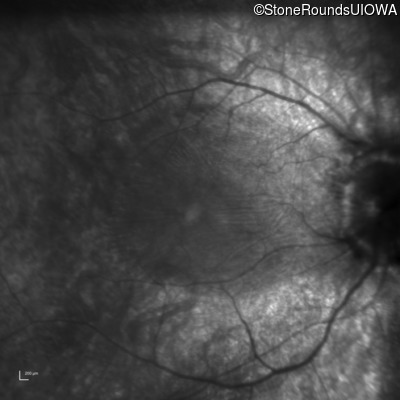

Age at visit: 16 years

This 16 year old female has had poor visual acuity and poor vision in dim light for most of her life. She has normal hearing and no cognitive difficulties.

SECORD RPE65 IVS1+5 G>A Arg124Stop CGA>TGA AR